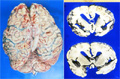

Macroscopic findings: Brain demonstrated atrophy mainly in the frontal lobe. Cerebral sulci widened with the gyri prominent. The cut surface (right) also revealed the widening of sylvian fissure, indicating massive cortical atrophy.